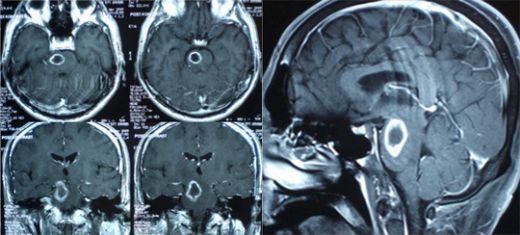

Beyin Biyopsisi Nedir?Beyin biyopsisi, beyin dokusunun bir parçasının alınarak laboratuvar ortamında incelenmesi işlemidir. Bu işlem, çeşitli beyin hastalıklarının tanısını koymak, hastalığın seyrini değerlendirmek veya tedaviye yönelik bilgi sağlamak amacıyla yapılır. Beyin biyopsisi, genellikle tümörler, enfeksiyonlar, iltihabi hastalıklar ve diğer nörolojik rahatsızlıkların değerlendirilmesinde kritik bir rol oynamaktadır. Beyin Biyopsisi Türleri Beyin biyopsileri, genel olarak iki ana kategoriye ayrılır:

Her iki tür, farklı durumlar ve hastalıklar için uygun olabilmektedir. Açık biyopsi, genellikle cerrahi müdahale gerektiren durumlarda yapılırken, perkütan biyopsi, daha az invaziv bir yöntem olarak tercih edilmektedir. Beyin biyopsisi süreci, birkaç aşamadan oluşur:

Bein Biyopsisi Süreci hakkında bilgi edinmek gerçekten önemli bir konu. Bu işlem, genellikle belirli bir beyin lezyonunu değerlendirmek amacıyla yapılır. İşlem öncesinde hastaların detaylı bir muayene ve görüntüleme yöntemleri ile değerlendirilmeleri gerekiyor. Stereotaktik cerrahi yöntemi, bu süreçte daha az invaziv bir yaklaşım sunarak hassas bir şekilde örnek almayı sağlıyor.